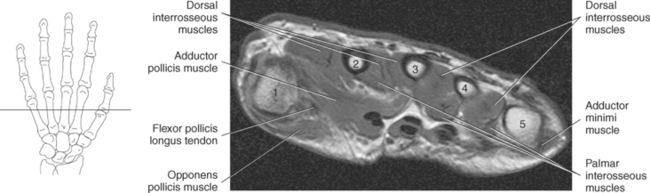

Figure 9.132 Axial CT scan through fingers.

Key: fl, Flexors; c, capitate; ex, extensor tendons; r, radius; l, lunate; D, dorsal interosseus muscles; P, palmar interosseus muscles.